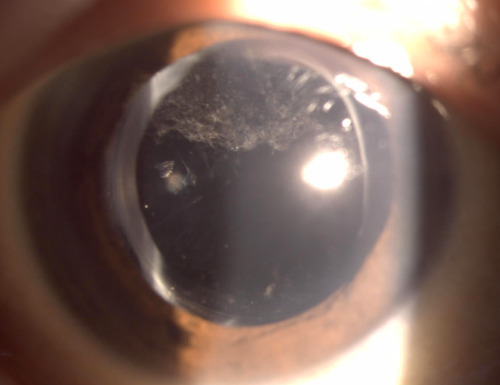

최근에 찍은 우안 세극등 사진입니다.